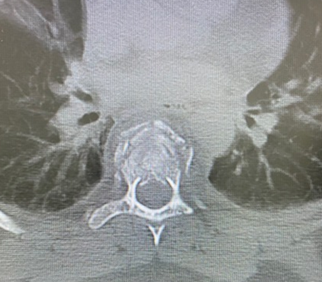

The patient underwent decompression by a posterior approach, and arthrodesis was performed with short instrumentation at T5-T6 (fractured vertebra - instrumented) -T7. The procedure presented some technical difficulty due to atypical bone anatomy with the presence of hypoplastic pedicles. The in-out-in technique was used to position the screws in the pedicles with smaller diameter (Figure 2). The patient progressed well in the immediate postoperative period, and she presented no complaints, no deficits, and good postoperative wound healing after the 3 and 6 month follow-ups. However, radiological control showed fusion failure, worsening of kyphotization, and instrumentation with an anomalous pathway (Figure 3). After analyzing the images, a surgical re-approach with expansion of the levels of arthrodesis was chosen.

Figure 3 Kyphotization with instrumentation failure.